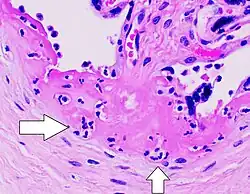

Histopathology of acute subchorionic intervillositis, with neutrophils in Langhan’s layer of fibrinoid (by the fetal surface, at the base of a chorionic villus, seen at top right).